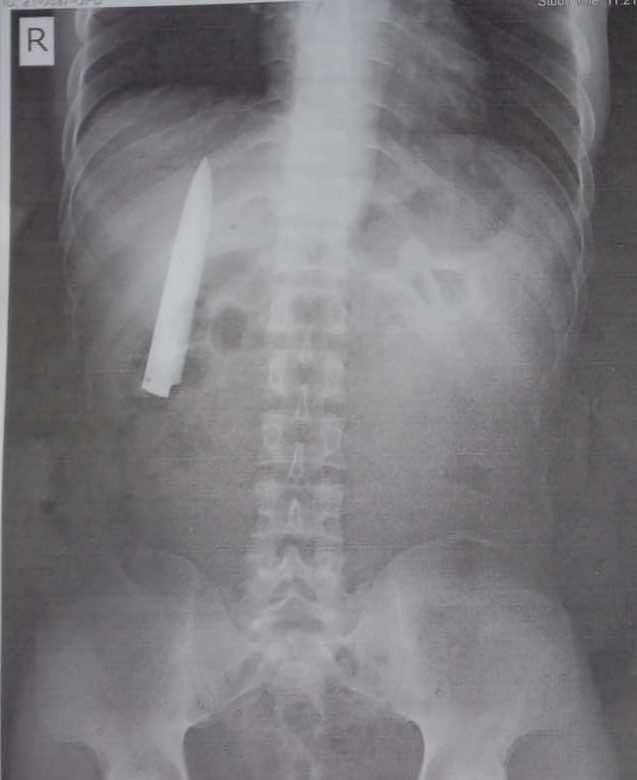

现在已经有一段时间了,塔莫感觉到持续不断的胸痛,尤其是在低温下。后来,在例行的X射线检查中,菲律宾人发现他的胸部有一个四英寸长的刀具。

25岁的塔莫(Tamao)X射线表明他的胸部一个位置停滞不前,他的X射线表明他的X射线表明他的X射线射程停滞不前,感到震惊和困惑。更令人震惊的是,刀子看起来像是他的一个肺之一。这个家伙没有意图进行X射线检查,并且没有做到跟踪他永恒痛苦的原因,但实际上,这是菲律宾人申请的一项采矿工作,这是强制性的。

“我总是想知道为什么天气寒冷时我会感到胸部有些疼痛。但是我不知道我的胸部有一把刀。”托马告诉当地的广播电台。

当医生问塔莫如何进入胸部时,他回答说,他大约一年前就被刺伤了受害者。当一群男孩袭击他时,肯特正在骑自行车。他对这一事件的了解不多,因为他当时还没有意识。他可以回忆起他在受伤严重的状态下被带到医院时在生与死之间作战的几乎没有。